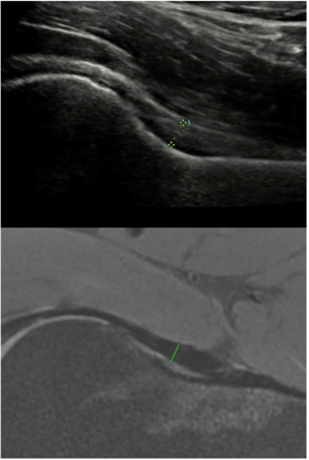

超声测量关节囊厚度

此外,我科进一步进行深入研究,评估超声检查作为MRI替代方法在临床评估髋关节囊厚度的可行性,研究发现通过超声和MRI获得的关节囊厚度测量结果显示出良好的一致性,表明超声可以在临床实践中替代MRI来测量髋关节囊厚度。同时,检验了定性和定量超声标准在诊断前上髋臼盂唇撕裂中的诊断性能,研究发现盂唇异质性回声是诊断前上髋臼盂唇撕裂的敏感标准,盂唇旁囊肿、盂唇局部高回声区和股骨头颈皮下囊肿是特异性标准。通过超声测量的前上髋臼盂唇的横截面积可以作为定量标准来诊断髋臼盂唇撕裂,结合盂唇的定性标准可以提高诊断前上髋臼盂唇撕裂的灵敏度和准确度。

Gao G, Fang H, Zhou K, Mo Z, Liu J, Meng L, Wang J, Xu Y. Ultrasound had high accuracy in measuring hip joint capsule thickness. BMC Musculoskelet Disord. 2024 Jan 29;25(1):101.

Fu Q, Jiang L, Cui L, Gao G, Xu Y, Tian C, Xue H, Sun Y. Quantitative and Qualitative Ultrasound Evaluation for the Diagnosis of an Anterosuperior Acetabular Labral Tear. Ultrasound Med Biol. 2022 May;48(5):924-932.